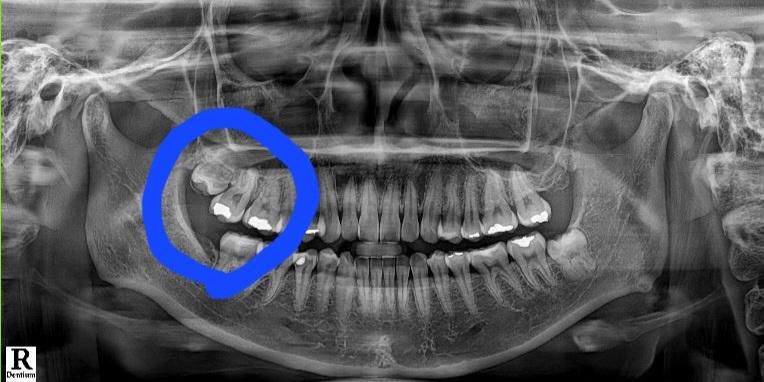

파란색동그라미부분쪽에 충치가 나서 치과에 갔더니 예전에 떼운 아말감들이 오래되어서 아말감을 다시 뜯고 크라운으로 덮어야한다고 하시네요. 아말감으로 한지 약 15년에서 20년정도 된것같긴합니다. 혹시나 과잉진료일수도 있다 생각해 의견을 물어보려고 생각해본다하고 나왔어요. 자세한것은 직접보고 진료받아야 정확하겠지만 이런경우가 있나요?

첫번째 큰 어금니 아말감 하방 이차충치가 의심됩니다 이차충치가 있을 경우 아말감은 일단 다 제거하고 내부상태본 뒤 다시 인레이를 하거나 아니면 충치가 깊을 경우 신경치료 후 크라운 씌우기도 합니다